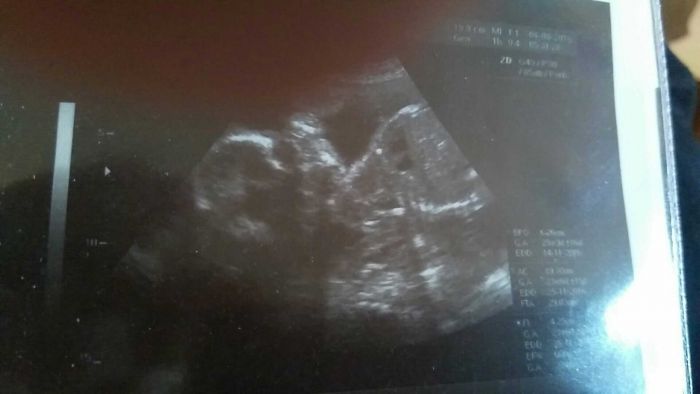

na fotce má hlavičku otočenou, ale vypadá jako by tam mělo očička i pusinku jak se usmívá